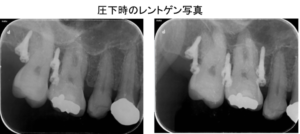

右下インプラント埋入直後のレントゲン写真です。

矢印部に下顎内の神経があり、これを避け、隣の歯と十分距離が保てるような位置でインプラントを埋入できました。